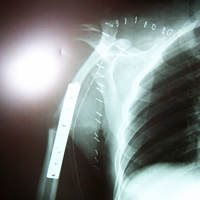

Case:6 Transfer of Scapula to Humerus

Orthopedic Oncology Doctor In Ahmedabad

Angio-2

Limb Reconstruction Doctor

Angiogram

Sports Injuries Doctor

Pre-op CTscan

Best spine surgeon in ahmedabad

Pre-Op X-ray

Best Trauma Surgeon

Biceps Tendon Re-Encoring

Joint Replacement

Specimen

Post Fixation

Post-op X-ray